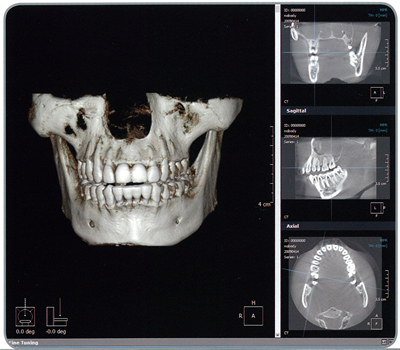

歯科用3DCT

3DCT

歯科用3DCT導入し、大規模病院と同じ診断と診療が可能です。

歯科用3DCTは、コンピューターを駆使したデータ処理と画像との再構成による3次元的な画像を作成することができ、360度全ての角度から見る事が出来ます。今までのX線では映らなかった部分も、はっきり映る様になりました。

また、放射線量も従来のアナログのオルソパントモの1/5のX線量です。

歯科用3DCT導入による3つのメリット

わかりやすい

立体的な画像を一緒に見ながら説明することにより、目で見て理解しやすく、今まで以上に納得して診療を始めていただけると考えております。診療に関して少しでも不安に思う事は何でもご相談ください。

歯科用3DCTで出来ること

従来、大規模病院でしか設備していなかった歯科用CTですが、よしもと歯科・矯正が導入してより正確な診断が出来る様になりました。以下の診療にとても効果的で、信頼性を高める事が出来ます。